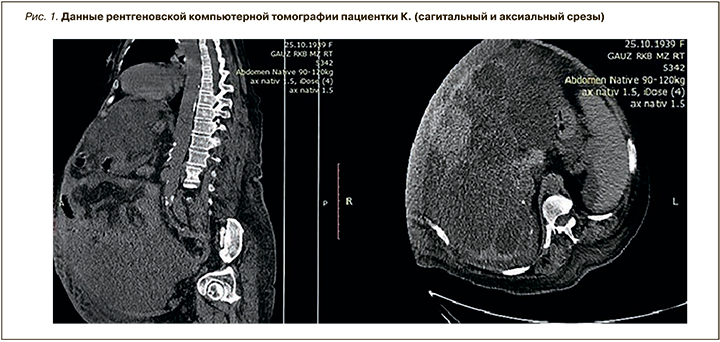

Для визуализации также была проведена рентгеновская компьютерная томография (рис. 1): структура печени неоднородная за счет множественных кист (размер одной из них – 157 мм), с кальцинированными стенками. Контуры почек деформированы, структура неоднородная за счет множественных кист, виден конкремент размером 10 мм. Жидкость в брюшной полости и малом тазу, остальные органы без особенностей.